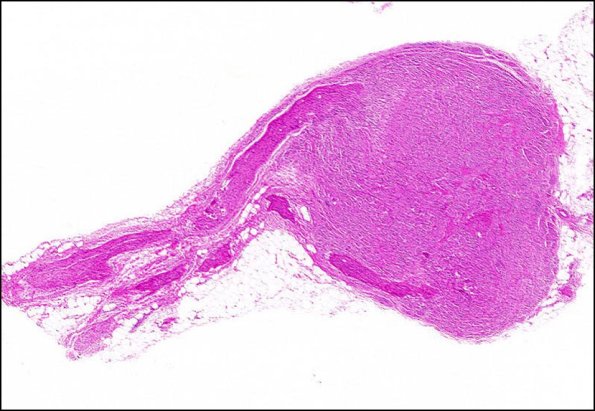

Washington University Experience | PERIPHERAL NEUROPATHY | 19 TRAUMATIC INJURIES | 1A1 Neuroma, traumatic (Case 1) H&E 2X

Case 1 History ---- The patient is a 62 year old woman with right ulnar nerve compression. Operative procedure: Transposition. ---- 1A1,2 At the end of this peripheral nerve is a haphazard proliferation of Schwann cells and nerve fibers with admixed collagen, forming a terminal nodular structure on the proximal nerve stump. (H&E)